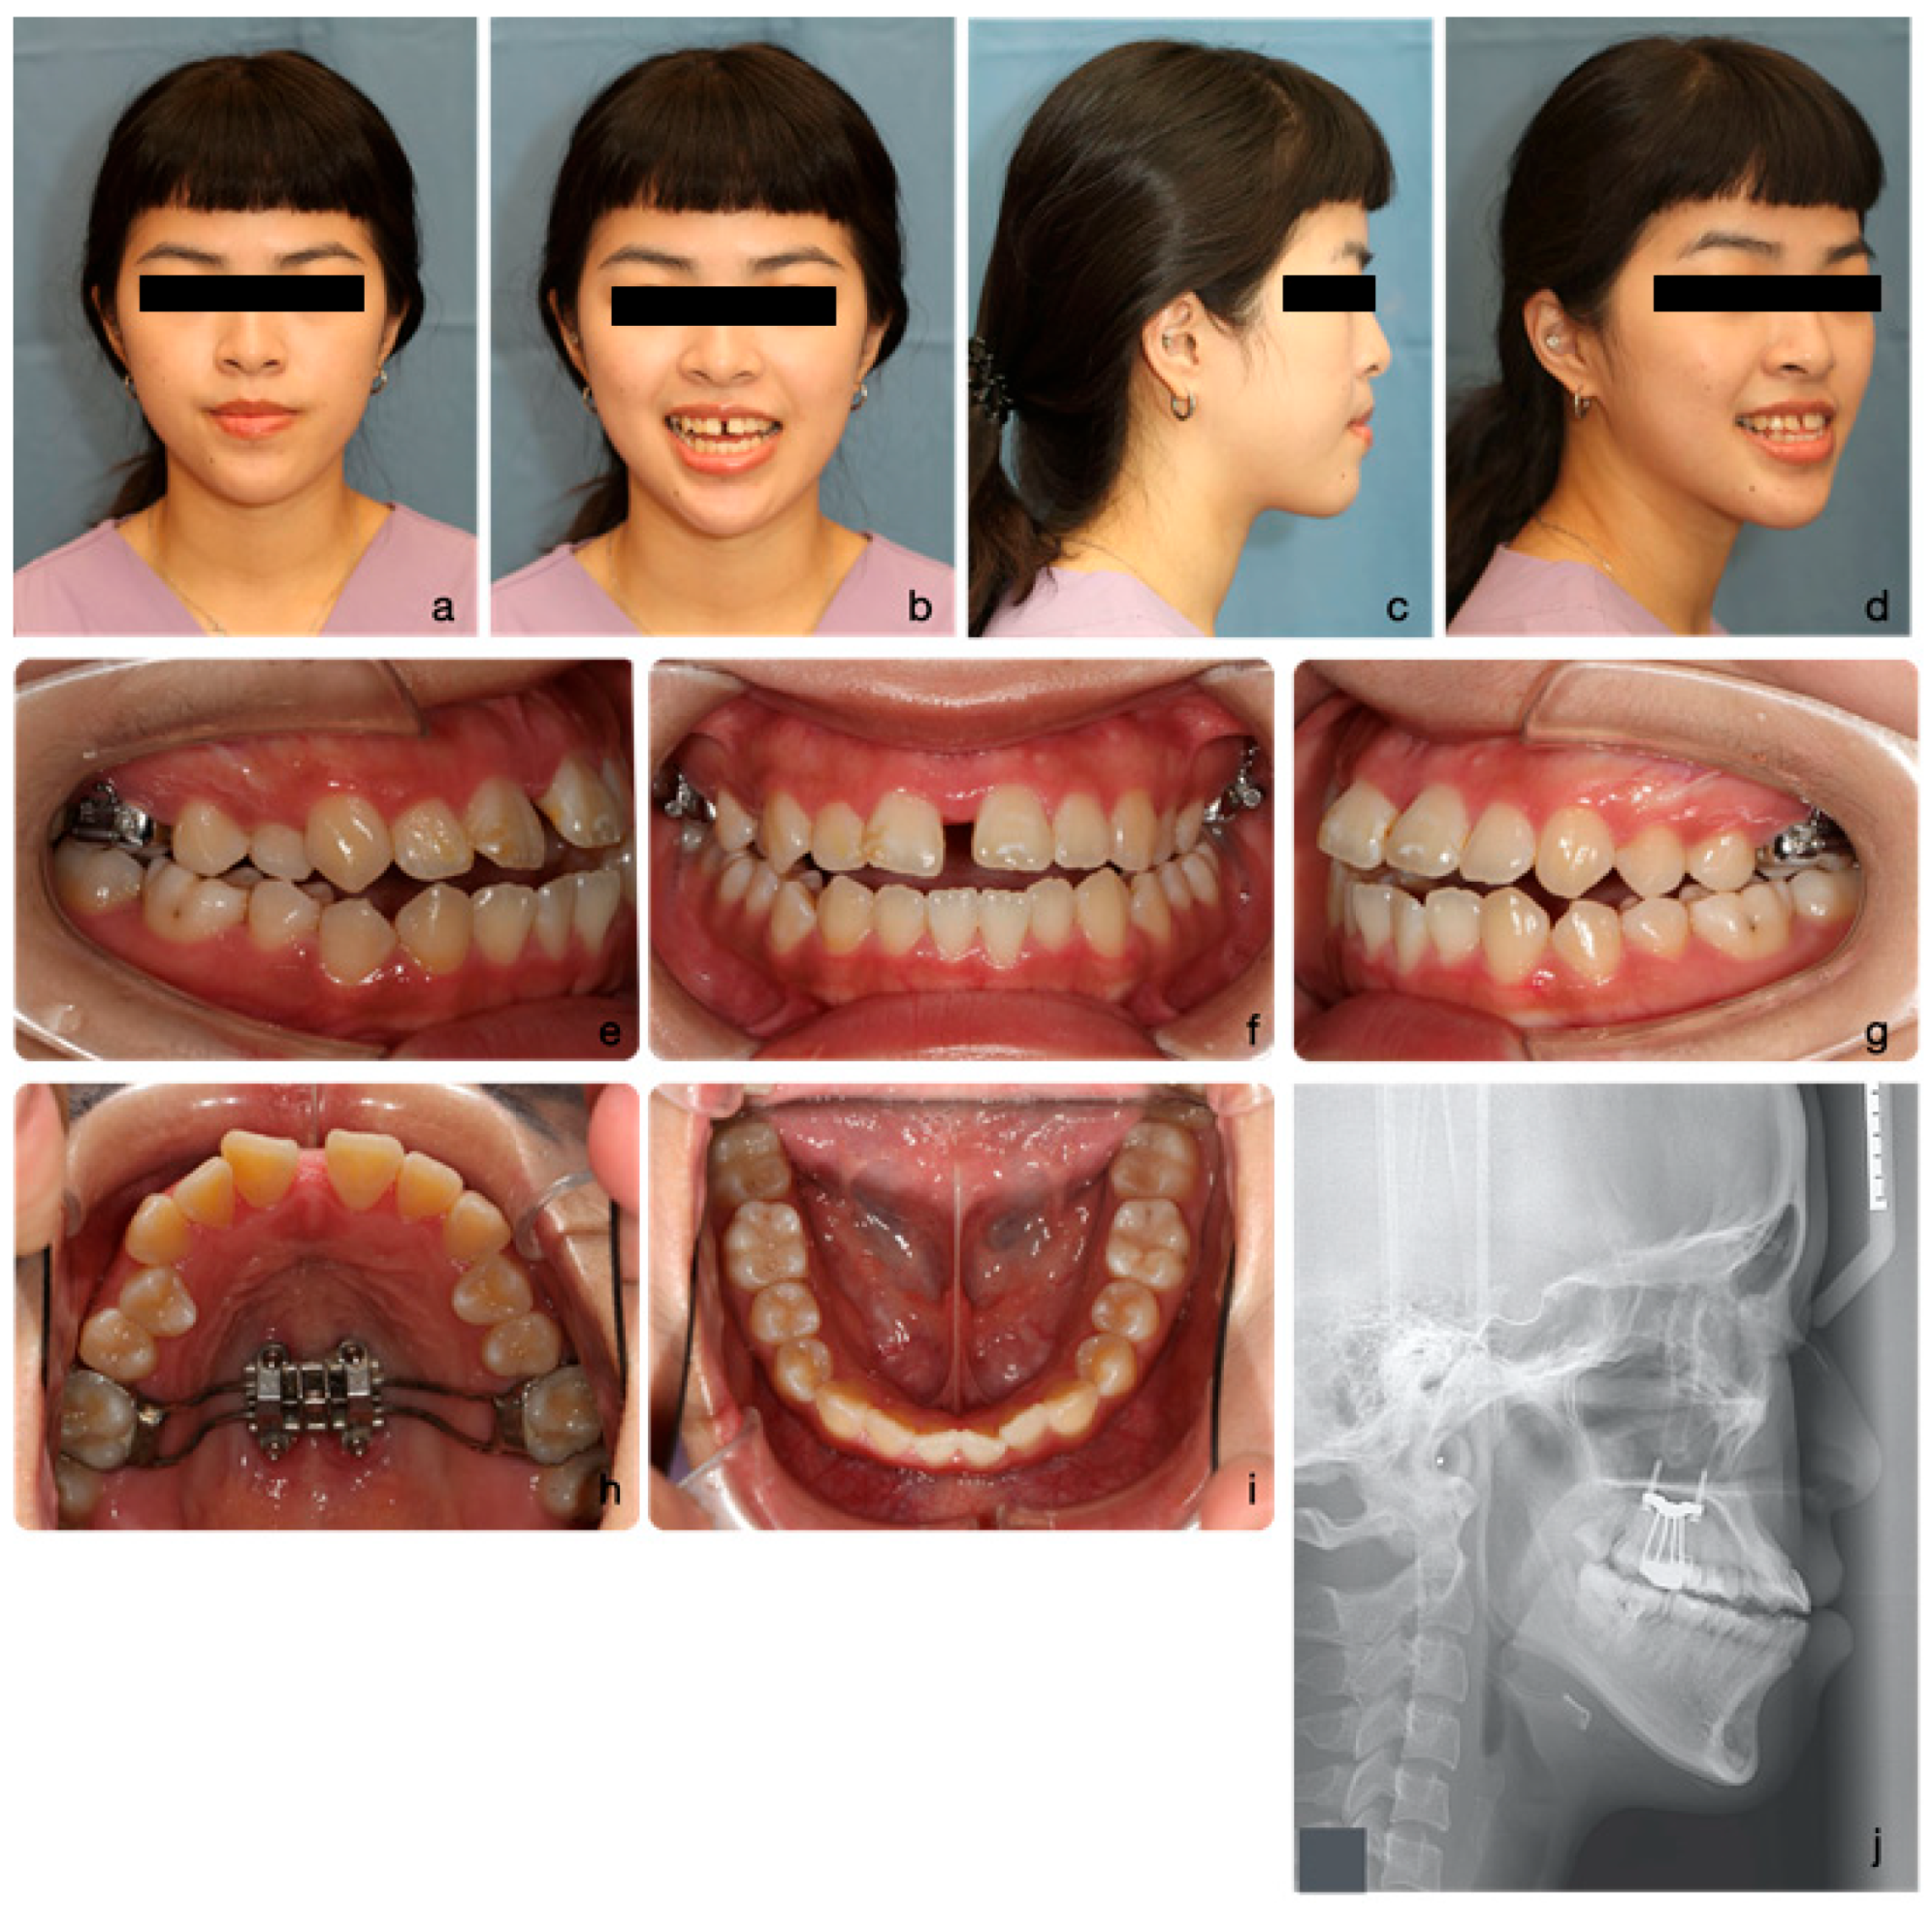

2.1. Diagnosis and Aetiology